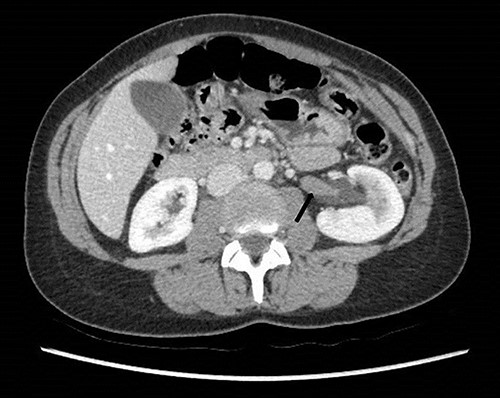

She underwent a flexible ureterorenoscopy 2 months later which further demonstrated no cause for hematuria within the collecting system. An ECHO cardiography was performed to out rule an embolic event to the kidney due to the patchy perfusion noted and was normal. A repeat CT angiogram showed resolution of the congestion of the left kidney, but a narrow LRV as before (Fig. 8).

Computed tomography angiogram 6 months later showing pre-compressed LRV (right arrow); and compressed LRV (left arrow), but resolution of the congestion and swelling of the left kidney.